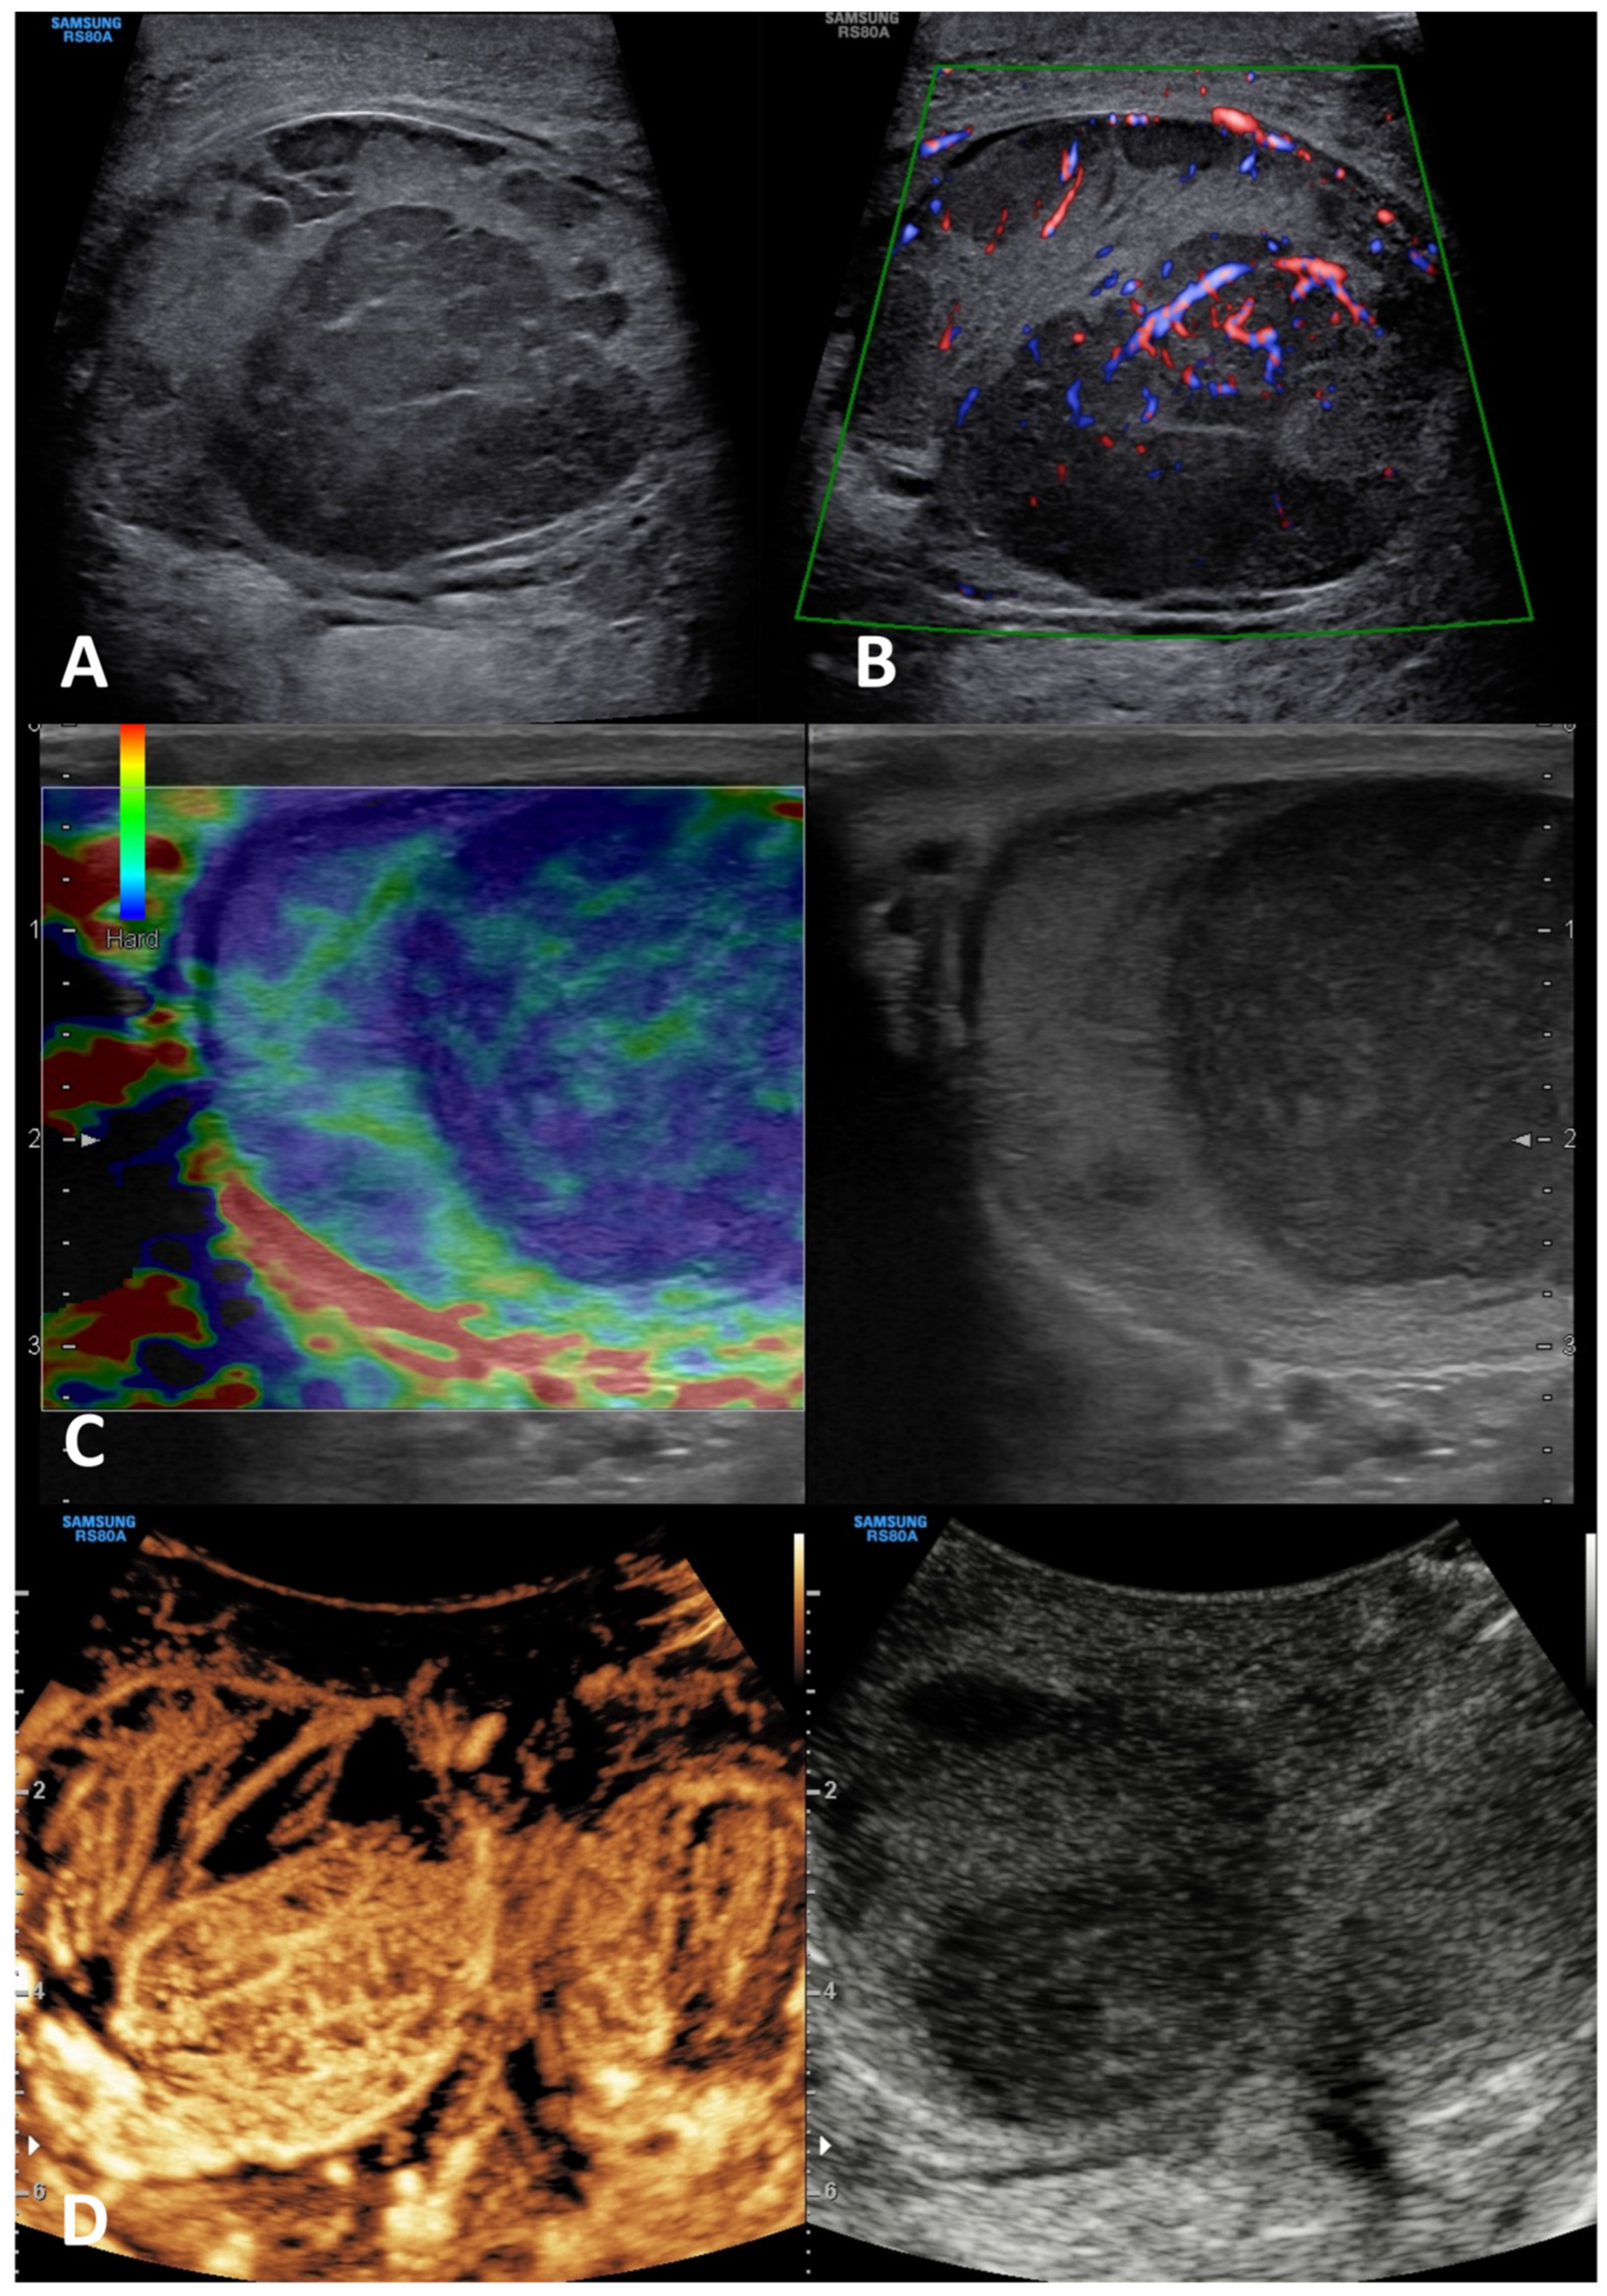

5.3.1. Leydig Cell Tumor (LCT)

| Leydig cell tumor | Generally asymptomatic; it can produce androgens | Negative | Hypoechoic, homogeneous well-demarcated lesion (possible hyperechoic halo) | Hypervascularized | Homogeneously hyperenhanced (rapid wash-in, delayed wash-out) | Hard lesions with low/absent elastic strain |

- Pozza, C.; Pofi, R.; Tenuta, M.; Tarsitano, M.G.; Sbardella, E.; Fattorini, G.; Cantisani, V.; Lenzi, A.; Isidori, A.M.; Gianfrilli, D.; et al. Clinical Presentation, Management and Follow-up of 83 Patients with Leydig Cell Tumors of the Testis: A Prospective Case-Cohort Study. Hum. Reprod. 2019, 34, 1389–1403. [Google Scholar] [CrossRef]

- Drudi, F.M.; Valentino, M.; Bertolotto, M.; Malpassini, F.; Maghella, F.; Cantisani, V.; Liberatore, M.; De Felice, C.; D’Ambrosio, F. CEUS Time Intensity Curves in the Differentiation Between Leydig Cell Carcinoma and Seminoma: A Multicenter Study. Ultraschall Med. 2016, 37, 201–205. [Google Scholar] [CrossRef]

- Samson, M.; Peale, F.V., Jr.; Frantz, G.; Rioux-Leclercq, N.; Rajpert-De Meyts, E.; Ferrara, N. Human Endocrine Gland-Derived Vascular Endothelial Growth Factor: Expression Early in Development and in Leydig Cell Tumors Suggests Roles in Normal and Pathological Testis Angiogenesis. J. Clin. Endocrinol. Metab. 2004, 89, 4078–4088. [Google Scholar] [CrossRef] [PubMed]